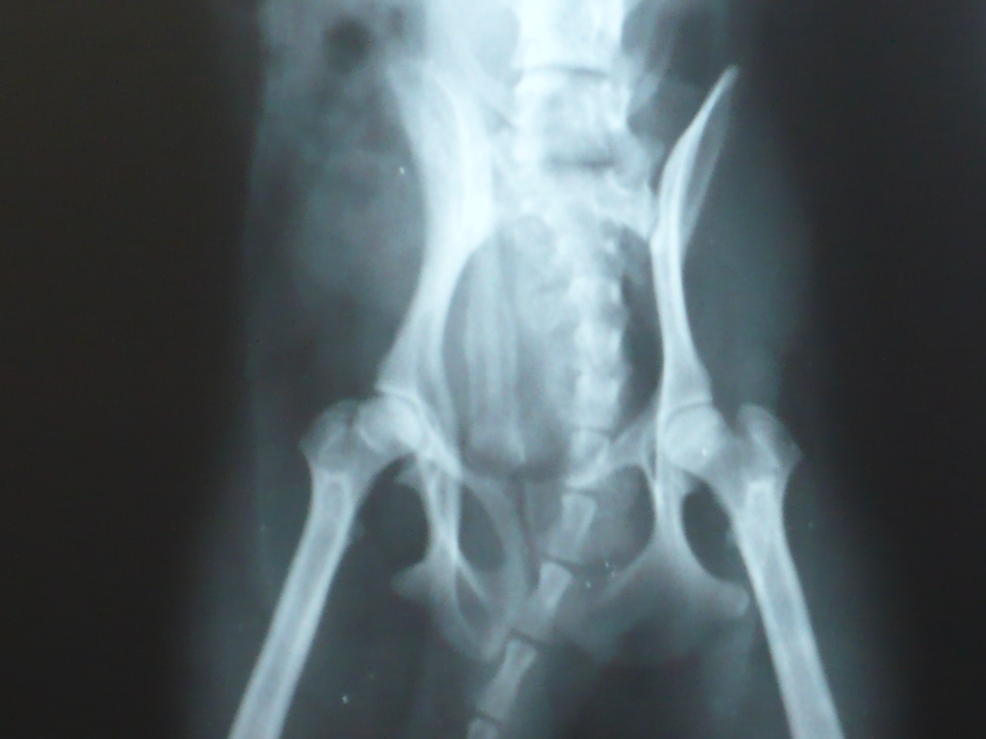

Вот снимок с разным увеличением суставов Микуши. yamagutti, обратите, пожалуйста, внимание и на скакательные суставы, хоть их и мало видно

• 1_1.JPG

Чихуахуа (1.JPG)

169,1 KB · Просмотры: 201

• 1_2.JPG

Чихуахуа (2.JPG)

238,2 KB · Просмотры: 206

• 1_3.JPG

Чихуахуа (3.JPG)

246,3 KB · Просмотры: 208

• 1_4.JPG

Чихуахуа (4.JPG)

299,4 KB · Просмотры: 214